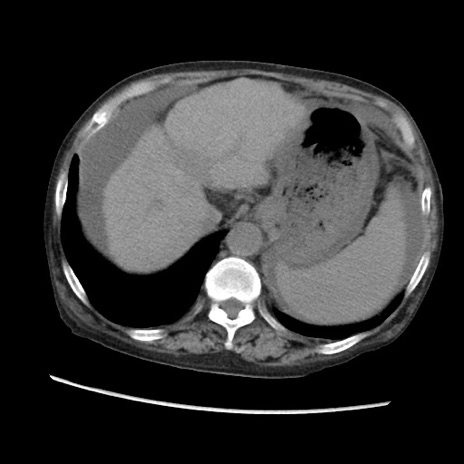

症例31(横断像)

【症例】80歳代 女性

【主訴】腹部膨満感

【現病歴】他院にて肝硬変にてフォロー中。1週間前から便秘、腹部膨満感、臍部腫瘤あり受診となる。

【既往歴】肝硬変

【身体所見】腹部膨隆あり、皮膚変化なし、疼痛なし。

【データ】WBC 4600、CRP 0.25